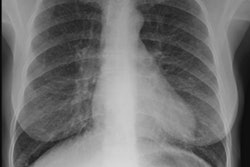

CXR: The radiologic features reflect DAH with patchy or bilateral diffuse airspace consolidation and GGO [1]. DAH may be more prominent in the perihilar areas and in the middle and lower lung zones (sparing the apices and CP angles) [2].